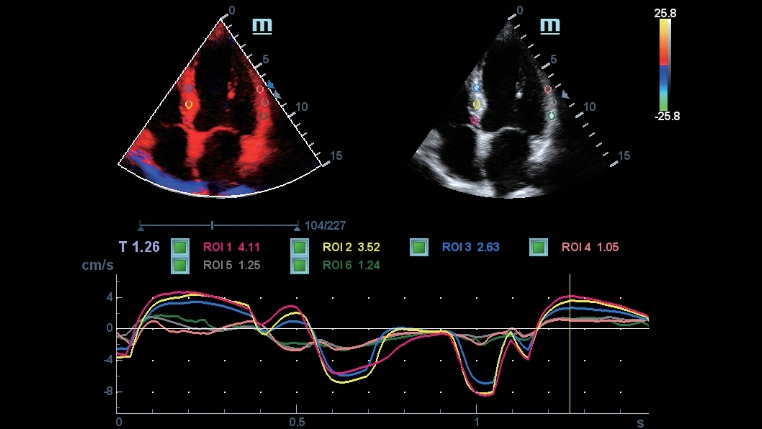

iTouch

DC-40 Full HD posiada pe?ny zakres narz?dzi, które maksymalnie zwi?kszaj? precyzj? diagnostyczn? i s? wygodne w u?ytkowaniu. W badaniach ogólnych, po?o?niczo-ginekologicznych i kardiologicznych, aparat DC-40 Full HD dostarcza kompleksowe rozwi?zania dla wielu zastosowań klinicznych, z uproszczonym cyklem pracy, zwi?kszaj?cym wydajno??.